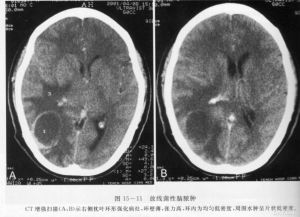

3、神經系統症狀:多見於嚴重感染。成蟲寄生於腦內時可出現癱瘓、麻木、失語、頭痛、嘔吐、視力減退等。成蟲侵入脊髓時可產生下肢感覺減退、癱瘓、腰痛、坐骨神經痛等。